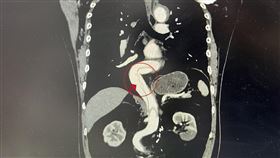

天冷打噴嚏撕裂血管 主動脈一路裂40公分

台中市1名65歲男子,在戶外工作時因天冷突然打了一個...